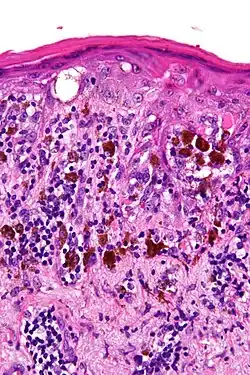

Lentigo maligna is where melanocyte cells have become malignant and grow continuously along the stratum basale of the skin,[1] but have not invaded below the epidermis.[2] Lentigo maligna is not the same as lentigo maligna melanoma, as detailed below. It typically progresses very slowly and can remain in a non-invasive form for years.

Lentigo maligna is a histopathological variant of melanoma in situ.[6] Lentigo maligna is sometimes classified as a very early melanoma,[7] and sometimes as a precursor to melanoma.[8]

Characteristics include a blue/black stain of skin initially. Skin is thin, about 4-5 cell layers thick, which is often related to aging. Histological features include epidermal atrophy and increased number of melanocytes.